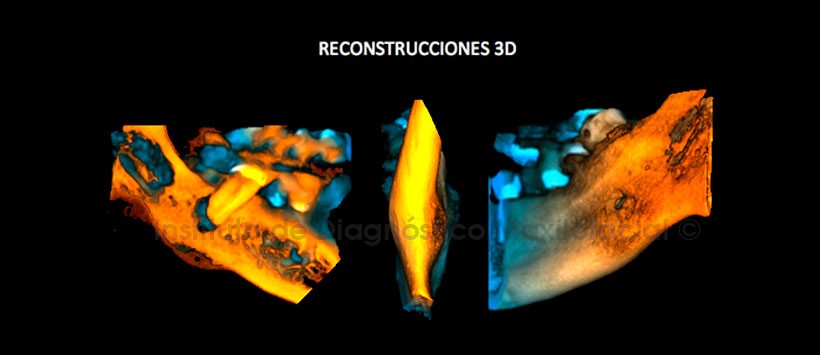

En las reconstrucciones 3D (Figuras 4 y 5) se aprecia con detalle la afectación ósea generada por el proceso osteolítico periapical de la pieza 47, trayecto fistuloso y reacción periostal.